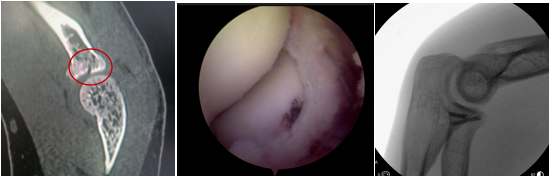

术前(左图)关节镜下(中图)术后即刻(右图)

通过肘关节镜微创手术,胡俊生副主任医师手术团队为小杨进行了关节镜辅助下左桡骨小头骨折复位内固定术,探查发现桡骨小头关节面骨块碎裂,骨折断端周围散在血凝块,仔细清理后在镜下复位后固定,仔细清理完周围滑膜组织后手术顺利结束。